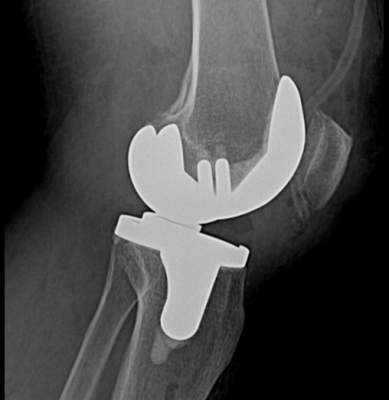

Gần đây nhất là trường hợp chị L.T.L.H 68t ở Duy Xuyên, đau khớp gối 2 bên Trái > Phải nhiều năm, đã điều trị tích cực nội khoa, tiêm nội khớp cũng như phẫu thuật nội soi cắt lọc khớp gối Trái nhưng không cải thiện, khớp gối Trái đau liên tục, đi lại hạn chế, trên X-Quang bắt đầu có biến dạng lệch trục vẹo trong gối, ảnh hưởng đi lại, sinh hoạt cũng như chất lượng cuộc sống. Chị H đã được các bác sĩ khoa Chấn thương chỉnh hình bệnh viện Vĩnh Đức thực hiện phẫu thuật cắt bỏ phần sụn khớp bị hư hại và thay khớp gối nhân tạo chân trái. Hiện sau quá trình phẫu thuật và tập vật lý trị liệu sau mổ, chị đã có thể tự đi lại không cần hỗ trợ, giảm đau khớp gối và không còn nghe tiếng “lạo xạo” mỗi khi hoạt động gấp duỗi gối như trước.

X-Quang sau mổ thay khớp gối toàn phần của BN L.T.L.H